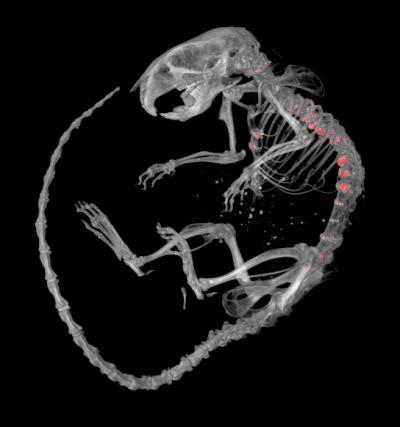

This is a micro-CT image of mouse skeleton, showing excessively mineralized lesions (in red) along the spinal column and sternum (breastbone).

(Photo Credit: Western University)